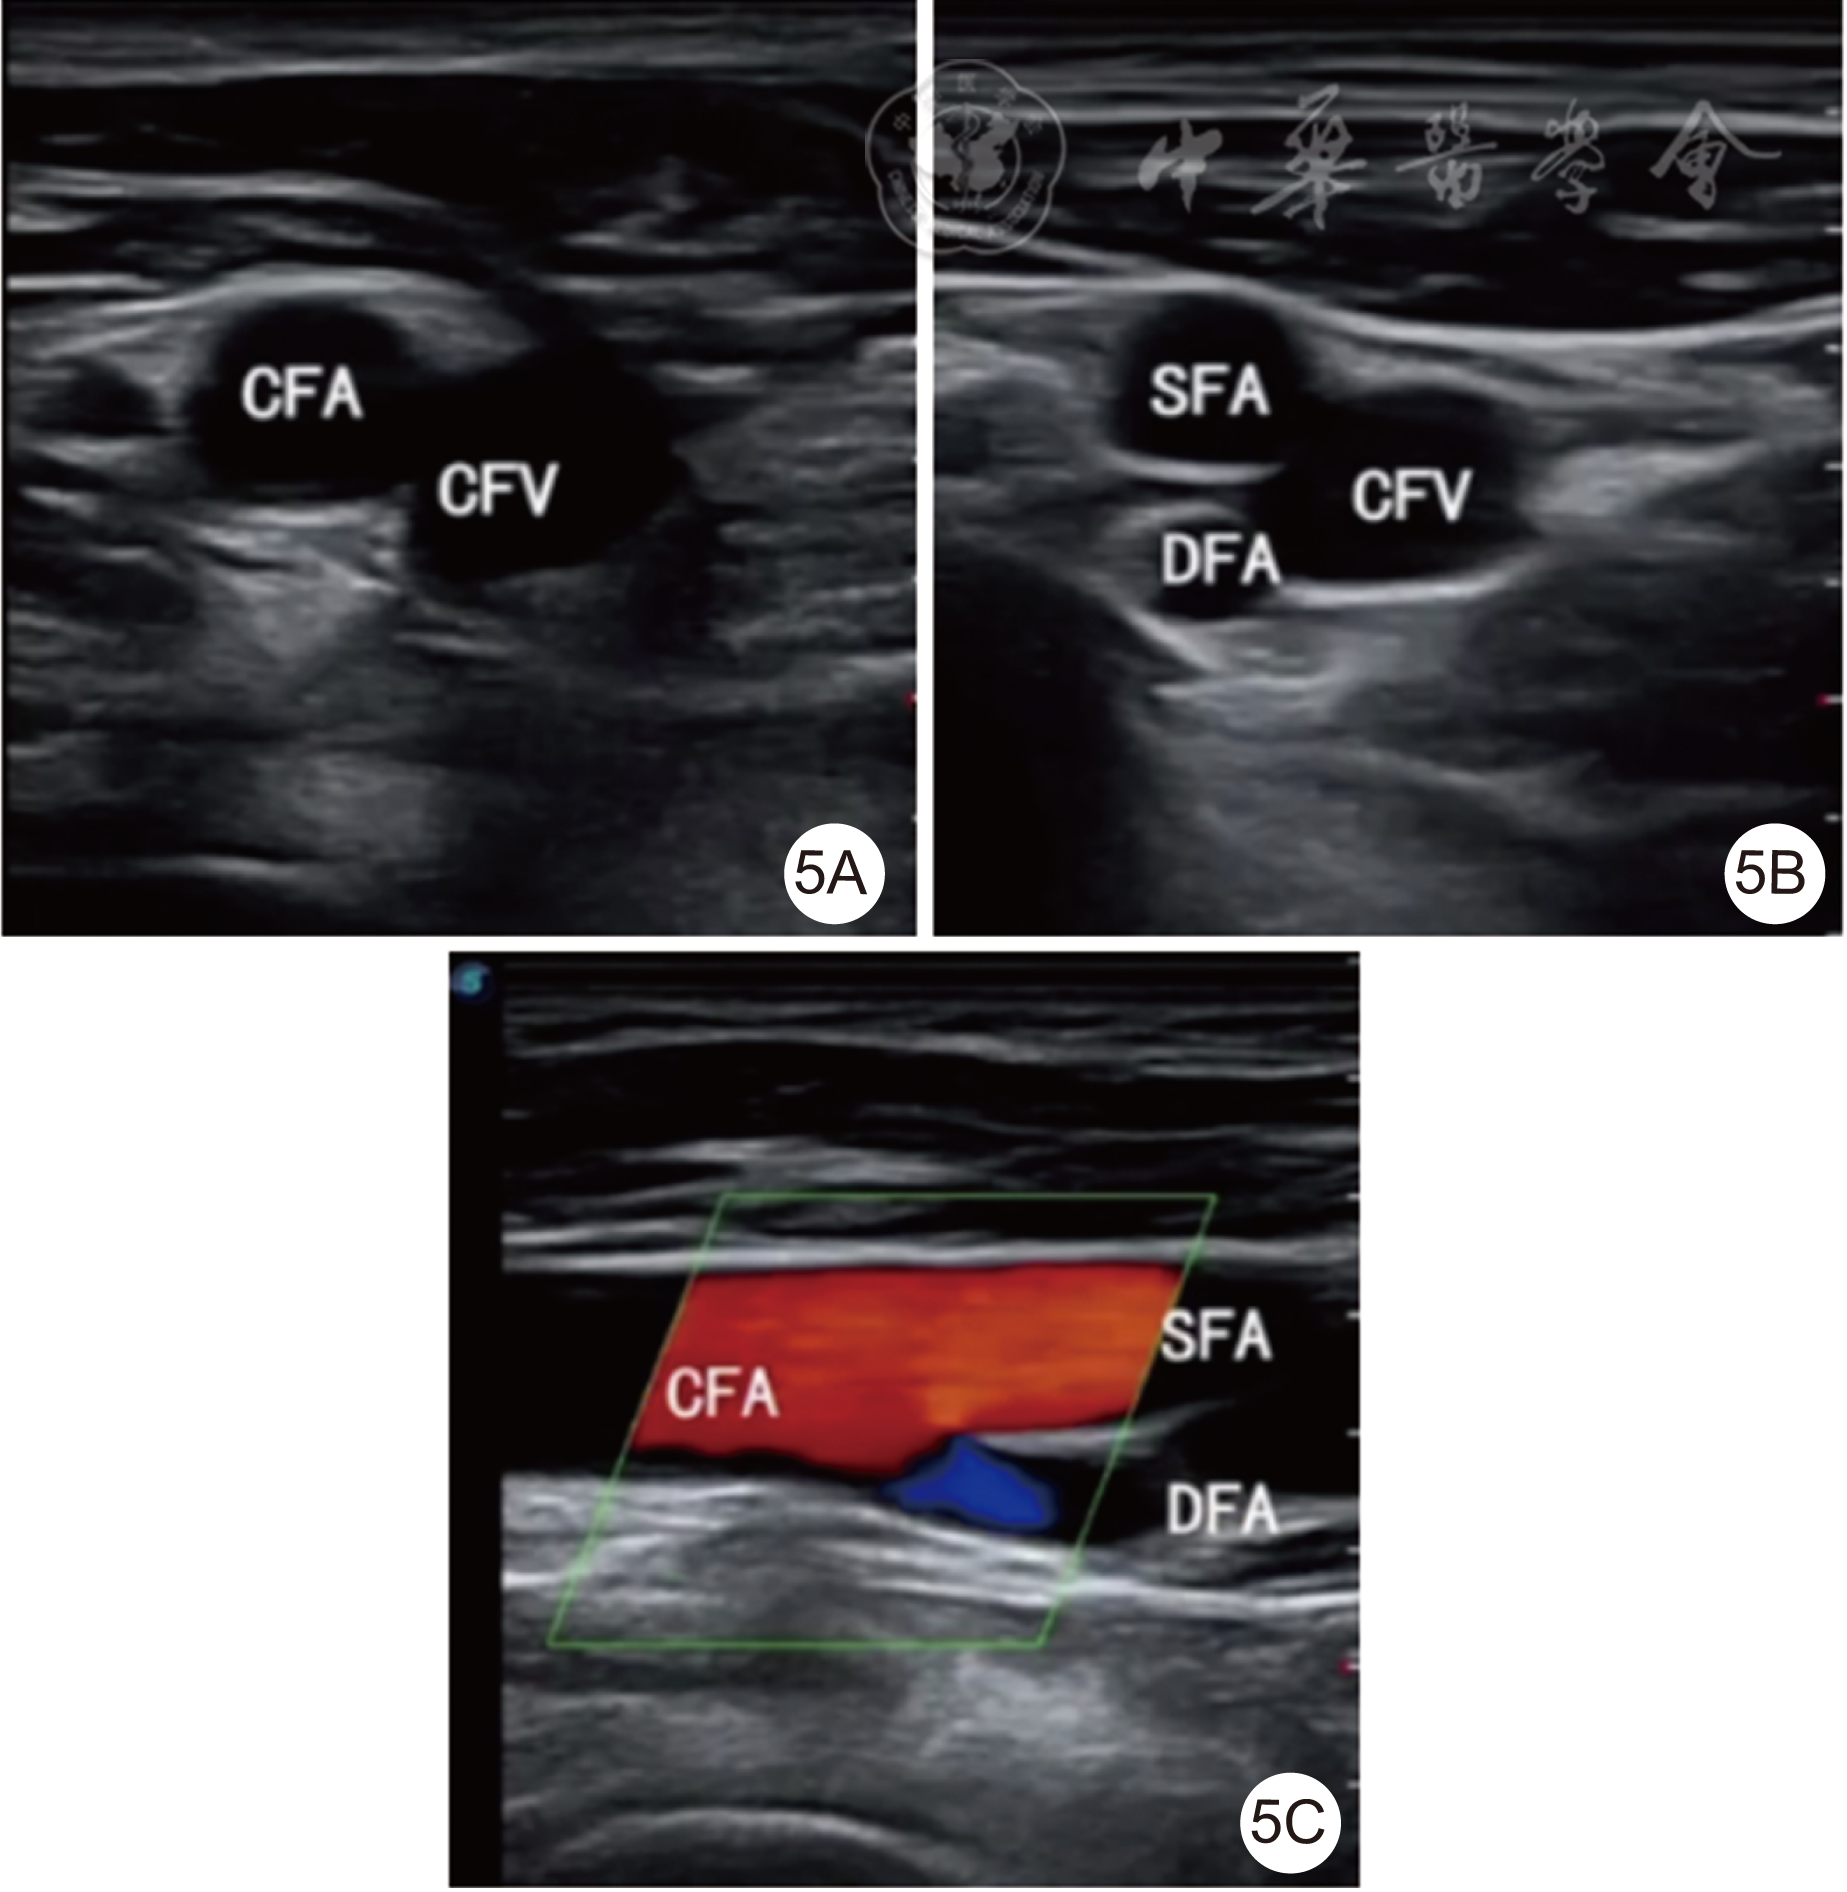

图5 二维血管彩超探查股、动静脉空间位置,指导精准血管穿刺过程(5A为短轴示股总静脉位于股总动脉内侧;5B为探头稍下移,短轴示股深动脉、股浅动脉及股总动脉位置关系;5C为转动探头,长轴示股总动脉、股浅动脉、股深动脉的空间位置关系)CFA为股总动脉,CFV为股总静脉,SFA为股浅动脉,DFA为股深动脉